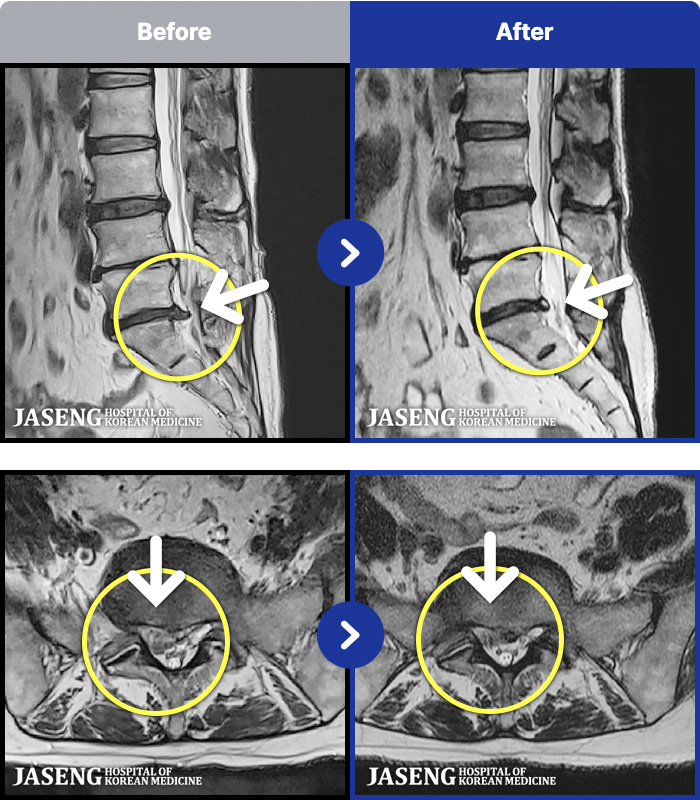

.png)